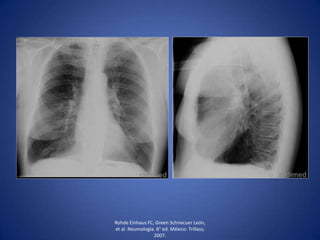

• Cuando además de líquido, existe aire en la cavidad

pleural (fístula broncopleural o introducción accidental

de aire a la cavidad pleural durante una punción).

• Líquido se acumula en las partes declives y el aire en la

parte superior.

Hallazgos radiológicos de

hidroneumotórax

• Opacidad homogénea que

borra senos

costodiafragmáticos,

cardiofrénicos y diafragma.

• Nivel hidroaéreo.

• Desplazamiento de la sombra

mediotorácica hacia el lado

contrario.